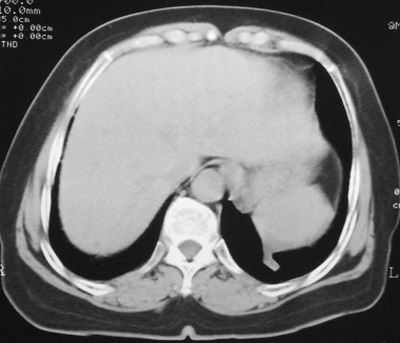

患者,女,64岁,4年前左腮腺"多形性"腺瘤手术治疗史.现复查胸部ct见左下肺块状影,该影与原左腮腺手术是否有联系?

表现:胸廓左右对称,气管居中,两肺野纹理增多,左下肺见一高密度影,周围见纤维条索影,心影及肺门无增大,双肋膈角锐利,横膈未见异常。

本次复查胸部ct

左下肺后基底段实性肿块,周围有毛刺,病变周围有肺气肿,与降主动脉间有条带状影相连,病灶4年前查体发现,纵隔内未见肿大淋巴结。考虑.肺隔离症,建议增强扫描与周围型肺癌鉴别。